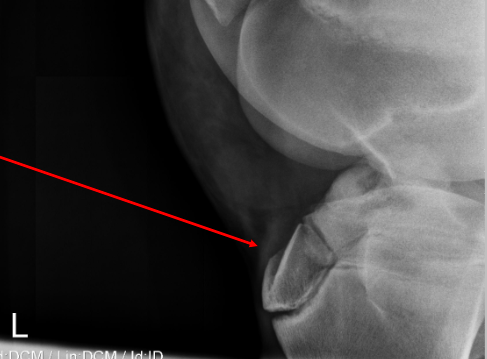

19

Q

label the bone types on this rad from top to bottom

A

• cortical bone (cortex)

• trabecular bone (medulla)

• subchondral bone (on articular surfaces/joints)

20

what is the top arrow pointing to?

a nutrient foramen